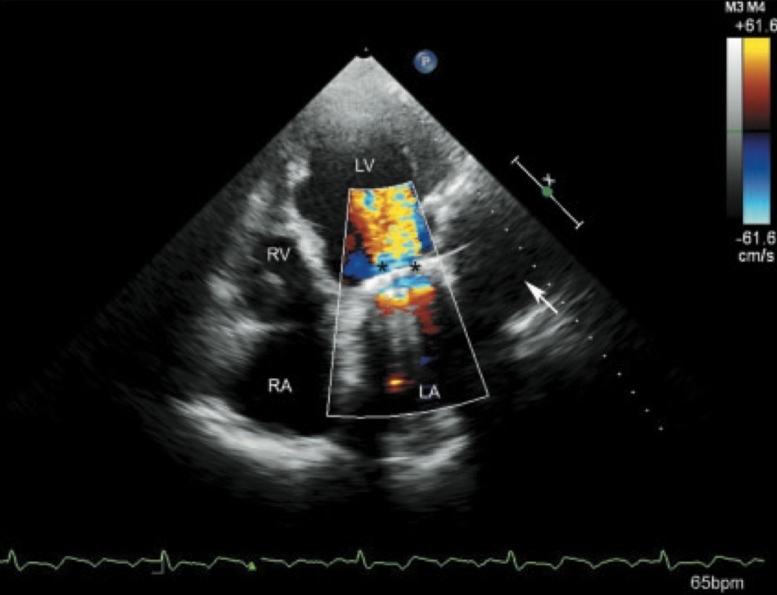

Laboratory investigations showed an elevated BNP of 210 pg/mL. Renal function, electrolytes, and fasting glucose were within normal limits (Table 1). Electrocardiogram revealed sinus rhythm with left ventricular hypertrophy. Transthoracic echocardiography revealed preserved left ventricular ejection fraction (60%), mild concentric left ventricular hypertrophy, left atrial enlargement, and grade II diastolic dysfunction (E/A ratio 1.7, E/e’ 16) (Figure 1).

The patient underwent follow-up assessments at 3, 6, and 12 months. At the 3-month visit, she reported improved exertional tolerance and resolved ankle edema, with BNP reduced to 180 pg/mL. By 6 months, minimal dyspnea was noted, lung sounds were normal, and BNP further decreased to 150 pg/mL. At 12 months, she remained asymptomatic, with normal examination findings and BNP of 120 pg/mL. Functional capacity was maintained through adherence to exercise and pharmacologic therapy (Table 2). Repeat echocardiography at 12 months demonstrated stable structural parameters and diastolic function (Figure 2).